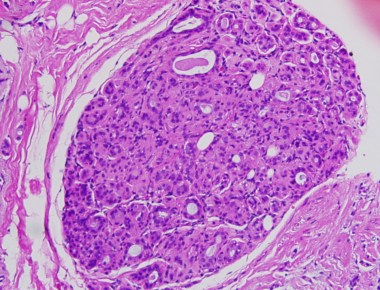

DCIS is the precursor lesion for most #malebreastcancer similar to female

Male breast cancer precursor lesions: analysis of the EORTC 10085/TBCRC/BIG/NABCG International Male Breast Cancer Program. Doebar SC, Slaets L, Cardoso F, Giordano SH, Bartlett JM, Tryfonidis K, Dijkstra NH, Schröder CP, van Asperen CJ, Linderholm […]